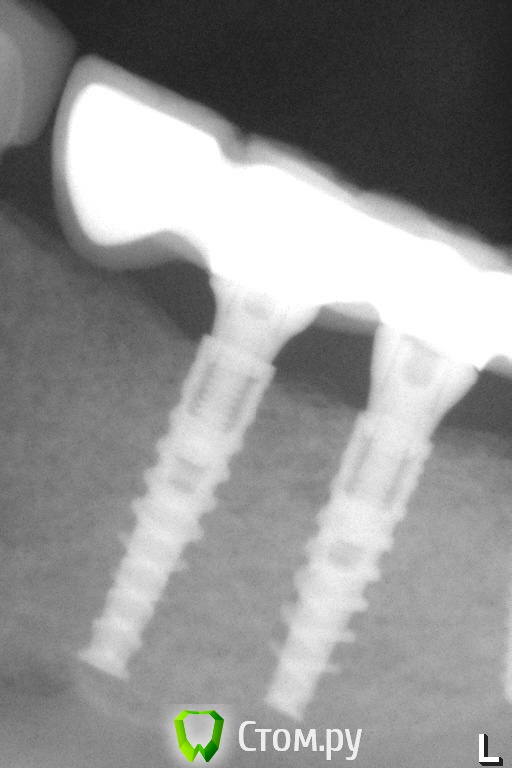

Pavel-Pskov Опубликовано 17 апреля, 2014 Поделиться Опубликовано 17 апреля, 2014 Есть несколько работ на узких имплантах 3.0 мм . Тоже маленько кость наросла. 3 Ссылка на комментарий

Pavel-Pskov Опубликовано 18 апреля, 2014 Автор Поделиться Опубликовано 18 апреля, 2014 Присоединяюсь к вопросу. Интересна первичная ситуация: какова ширина была?5-6 мм. Одномоментно с удалением. 41 и 31 были вообще не в кости 42 и 32 где то на 2-3 мм. Ссылка на комментарий

Pavel-Pskov Опубликовано 18 апреля, 2014 Автор Поделиться Опубликовано 18 апреля, 2014 альфа био ченджибл?ADIN NP. Сейчас еще интереснее тройки есть, пока наблюдаю. Ссылка на комментарий

Pavel-Pskov Опубликовано 18 апреля, 2014 Автор Поделиться Опубликовано 18 апреля, 2014 Разделом промахнулись.Я бы сказал - кость не наросла, кость не ушла после субкрестальной установкиНа RG где один имплант год назад , где два сейчас. Небольшая разница есть по моему. Ссылка на комментарий